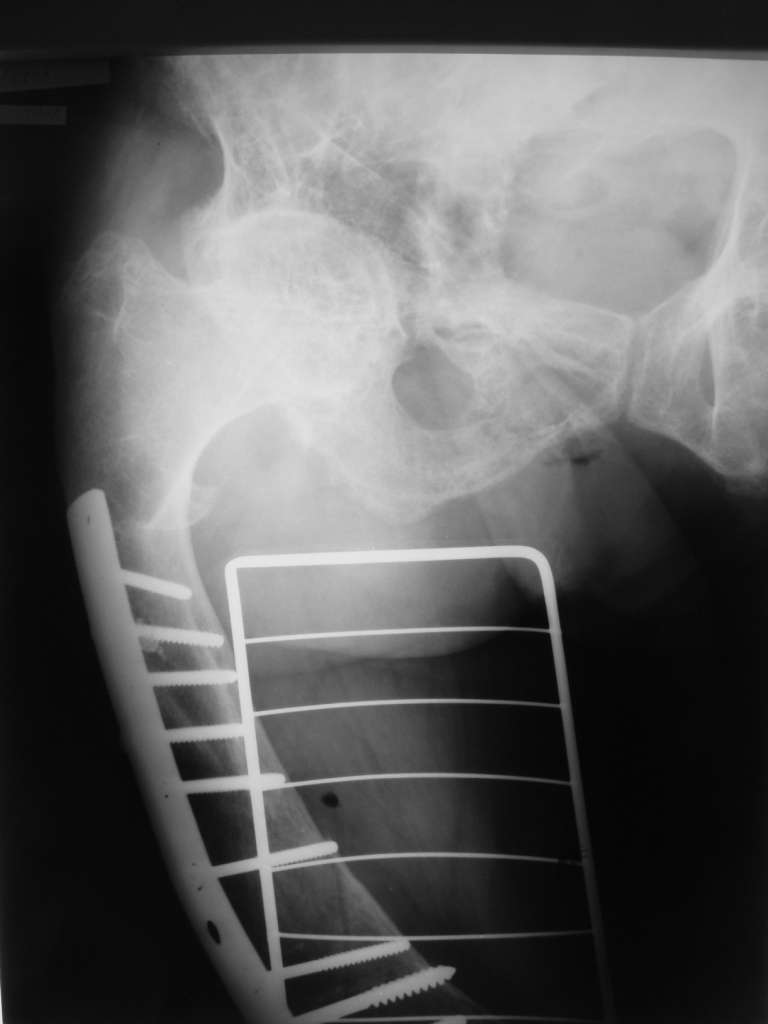

Но даже при малоинвазивной методике лечения применимой для даной больной существуют следующие проблемы: выраженный остеопороз, тонкий кортикал, очень широкий канал.

Контрольные рентгенограммы прилагаю.

А что доступно на месте? У нас бы голени зашифтовали закрыто стержнями диаметром 12 мм с запирающими винтами 6 мм производства предприятия "ЦИТО", Москва.

На месте доступно всё, даже стержни ЦИТО с небольшой задержкой.

Проблема в том, что в сагитальной плоскости угол голеней =30 градусам. Ширина канала 30.

Будет ли остеосинтез стержнем стабильный?

И возможны ли другие варианты остеосинтеза?